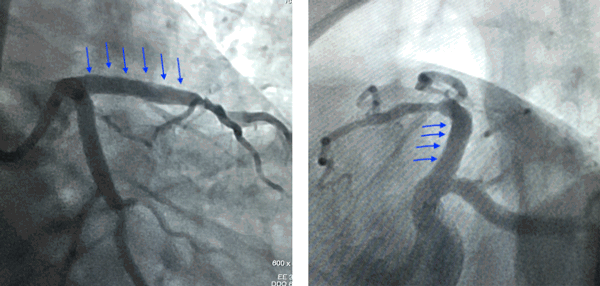

72 year old male with bronchitis and diabetes had severe Breathlessness since 3 days which progressed to Breathlessness on talking short sentences. ECG showed a massive heart attack. 2D ECHO showed that his heart pumping was reduced to only 40%.

Angiography showing badly calcified and diseased left anterior descending artery (lad) with a 100% block.

Based on this IVUS image, a large stent was deployed and the artery was opened and blood flow was restored.